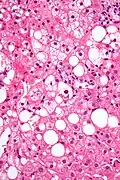

Micrograph showing a Mallory body with the characteristic twisted-rope appearance (centre of image - within a ballooning hepatocyte). H&E stain.

Mallory bodies are highly eosinophilic and thus appear pink on H&E stain. The bodies themselves are made up of intermediate cytokeratin 8/18 filament proteins that have been ubiquitinated, or bound by other proteins such as heat shock proteins, or p62/Sequestosome 1.[5]